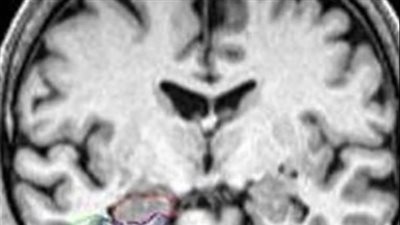

دراسة: شرب الماء يحميك من مرض الزهايمر

مرض الزهايمر، وهو نوع من الخرف، لا يُعالَج بالأدوية، كونه مرضًا عصبيًا معقدًا، ولكن العلماء أكدوا أنه يمكنك حماية نفسك من الإصابة بأمراض خطيرة بمساعدة المياه المعدنية.

نشر باحثون من جامعة كيل (ألمانيا) مقالاً يزعم أن الماء قد يكون وقاية فعّالة من مرض الزهايمر، وأوصى العلماء في هذا الصدد بشرب المياه المعدنية المُدعّمة بالسيليكون بانتظام.

يقول الخبراء إن أحد أسباب تطور مرض الزهايمر ومرض باركنسون والتصلب المتعدد هو تأثير الألمنيوم على الجسم، والذي يوجد على نطاق واسع في البيئة وله خاصية التراكم في جسم الإنسان.

يقول العلماء في المقال: "غالبًا ما تحتوي مياه الصنبور على مستويات منخفضة من حمض السيليكا، مما قد يساهم في ارتفاع مستويات الألومنيوم في الجسم لذلك، يُنصح بشرب المياه المعدنية المُدعّمة بالسيليكا بانتظام لإزالة الألومنيوم السام من الجسم والدماغ".

أظهرت تجاربهم أن شرب لتر واحد من الماء المعدني الغني بالسيليكون يوميًا يُسرّع من التخلص من الألومنيوم السام في البول وفي بعض الحالات، انخفضت مستويات الألومنيوم في الجسم بنسبة تصل إلى 70% خلال فترة 12 أسبوعًا من شرب الماء، مما ساهم في تحسين الوظائف الإدراكية، وفقًا للخبراء.